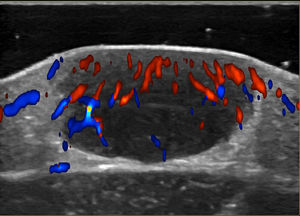

Doppler Ultrasound

Noninvasive techniques such as Doppler ultrasound can be useful alternatives to histology for assessing and monitoring lesions. Ultrasound findings include a well-demarcated hypoechoic nodule at the dermal-epidermal junction or in the dermis without posterior enhancement or lateral shadowing. In some cases, color Doppler ultrasound shows vascularization, with thin, slow-flow arteries within the lesion (Fig. 4).45,46